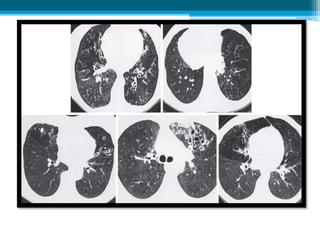

• #19 High-resolution CT scans of lungs with bronchiectasis. A, Dilated and thickened airways (arrow). B, Airways do not taper (arrows) toward the periphery in a patient with Kartagener syndrome. C, Varicose changes (dilated and beaded airways [arrows]). D, Clustered cysts or saccules (arrow) as well as a peripheral infiltrate. E, Middle lobe bronchiectasis (arrows) in a patient with Mycobacterium avium complex infection. (From Barker AF: Bronchiectasis, N Engl J Med 346:1383, 2002.)